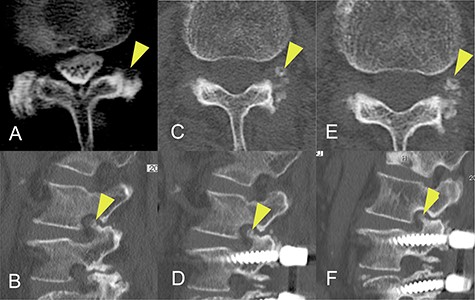

CT images acquired a few months before the onset of radiculopathy had shown a small isolated area of ossification, suggesting that the ossification site had gradually expanded to include the superior articular process over a period of months (Fig. 3).

Progression of ossification of the ligamentum flavum (OLF) on computed tomography (CT) images obtained before onset of radiculopathy. (A) OLF was not found on a CT scan obtained 8 years earlier. (B) A CT image obtained 20 months earlier shows a small isolated area of OLF in the foramen. (C, D) A CT image acquired 4 months earlier shows that the area of OLF had grown slightly and was integrated with the superior articular process. (E, F) A CT image obtained at the time of surgery shows further expansion of OLF.

The changes in CT findings over time in this case (Fig. 3) confirm that the ossification was initially confined to the ligamentum flavum but gradually expanded to the point where it constricted the nerve root at the foramen. However, our review of the literature did not yield any reports of OLF as a cause of radiculopathy at the foramen. Furthermore, although there are some reports on the classification of OLF, most did not include an isolated type. Sato et al. proposed that thoracic OLF be classified as lateral, extended, enlarged, fused or tuberous [14]. Mori et al. subsequently recommended a modified classification system based on whether OLF was small, medium, large, extra-large or central-type [6]. However, Saiki et al. identified four types of OLY, namely, spiny, placoid, nodular and isolated [15]. They also identified that 1% were of an isolated free type, which they defined as a form of ossification that is free in the ligamentum flavum and has no continuity with the articular processes. We consider that our case could be classified as the isolated free type of OLF originally described by Saiki et al. and suspect that this rare type of OLF may have been overlooked in more recent studies, particularly those using CT images. Furthermore, the radiographic and CT images obtained before the onset of radiculopathy in this patient were valuable in that we were able to confirm progression of OLF before the onset of symptoms.